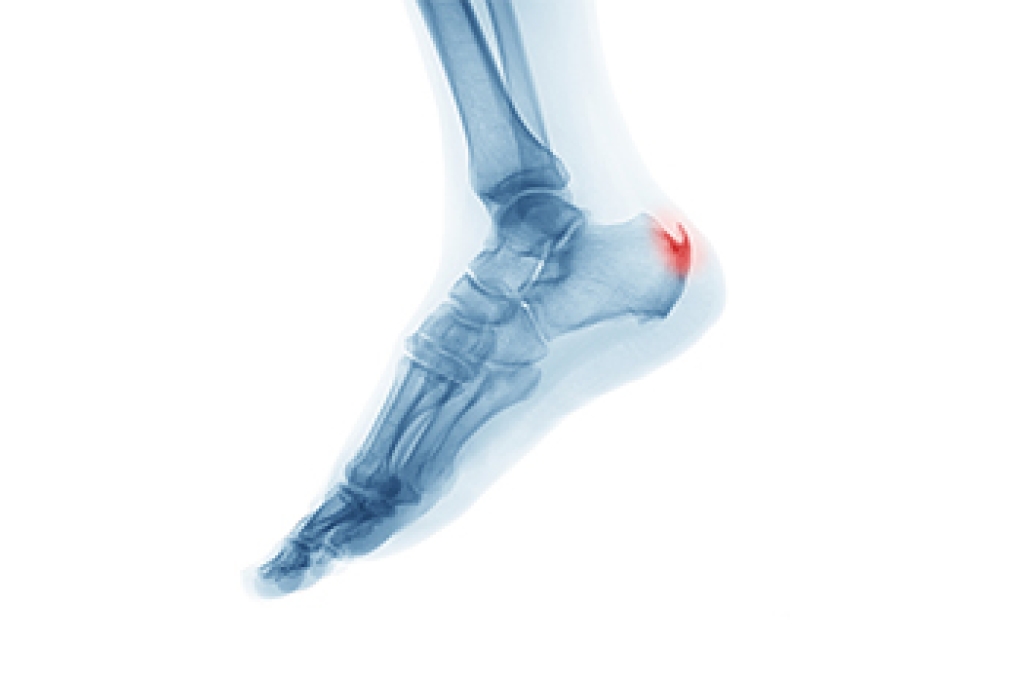

Many runners end up with heel spurs, often as the result of repetitive pounding on hard surfaces. A heel spur, also known as a calcaneal spur, is a bony protrusion on the underside of the calcaneus bone of the heel. Plantar fasciitis sometimes damages the membrane that covers the heel bone, making it more likely for heel spurs to form. Although heel spurs can become quite painful, many people develop them over time without knowing it. In general, it is not a heel spur itself, but damage to its surrounding tissue that causes the pain. Common causes of heel spurs include overstretching the plantar fascia, damage to foot muscles and ligaments, and wearing shoes that lack proper cushioning or arch support. Many nonsurgical treatments successfully reduce the pain, including cortisone injections, taping, custom orthotics, exercises, and replacing footwear. If your heel pain persists, it is a good idea to consult a podiatrist for an examination, a diagnosis, and an appropriate treatment.

Heel spurs are formed by calcium deposits on the back of the foot where the heel is. This can also be caused by small fragments of bone breaking off one section of the foot, attaching onto the back of the foot. Heel spurs can also be bone growth on the back of the foot and may grow in the direction of the arch of the foot.

The pain associated with spurs is often because of weight placed on the feet. When someone is walking, their entire weight is concentrated on the feet. Bone spurs then have the tendency to affect other bones and tissues around the foot. As the pain continues, the feet will become tender and sensitive over time.